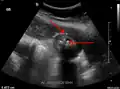

Imaging

Right upper quadrant abdominal ultrasound is most commonly used to diagnose cholecystitis.[1][26][27] Ultrasound findings suggestive of acute cholecystitis include gallstones, pericholecystic fluid (fluid surrounding the gallbladder), gallbladder wall thickening (wall thickness over 3 mm),[28] dilation of the bile duct, and sonographic Murphy's sign.[13] Given its higher sensitivity, hepatic iminodiacetic acid (HIDA) scan can be used if ultrasound is not diagnostic.[13][14] CT scan may also be used if complications such as perforation or gangrene are suspected.[14]

29. ^ a b "UOTW #30 - Ultrasound of the Week". Ultrasound of the Week. 23 December 2014. Archived from the original on 9 May 2017. Retrieved 27 May 2017.